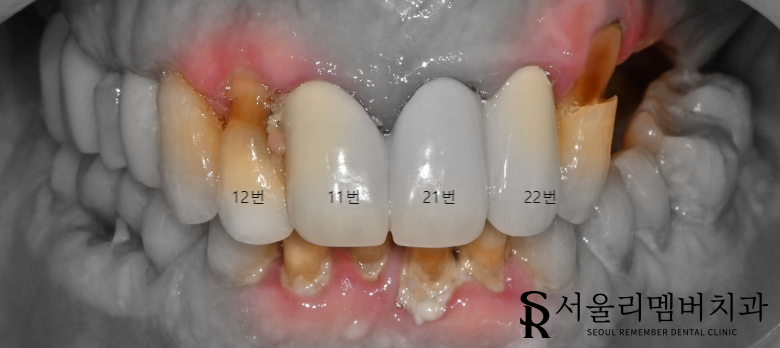

검진을 위해 엑스레이와 포토 촬영을 했습니다.

전체적으로 치아가 시리다고 하신 이유는

치경부 마모증이 심한 상태였기 때문이었는데요.

11,12번 치아 사이에 음식물이 많이 끼여있어

사진상으로 잘 보이지 않지만 caries가 생겨있었습니다.